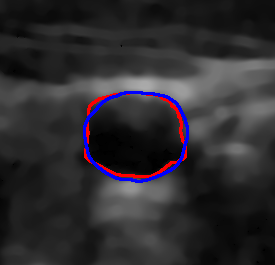

4.7 Downstream Task on Ultrasound Image Segmentation

To showcase the potential of the proposed denoising method quantitatively for ultrasound image understanding, we evaluate its impact on carotid ultrasound segmentation as a downstream task [9]. In this task, we use unseen noisy carotid images collected from the Clarius device. Then, unsupervised Segment Anything 2 (SAM2) [66] and the rule-based Flood Fill algorithm are used to extract the carotid artery from noisy and denoised images processed by various despeckling algorithms. In both cases, we place the seed point at the geometric center of the carotid lumen in each frame.

The quantitative result in terms of both IoU and AUC has been summarized in Table 6. To provide an intuitive visualization of the comparison, the results of SAM2 on a representative image and its denoised variants are presented in Fig. 12. It can be seen from Table 6 that the overall results using SAM2 are significantly improved in comparison to the Folld fill algorithm. This is primarily because of the strong generalization capability of the foundation model itself. Although the results produced by SAM2 across different images are comparable, the outcomes on images denoised by our method consistently demonstrate superior performance. The AUC reaches the highest score among all methods, while the IoU achieves the second-best performance. This performance advantage becomes more pronounced when using traditional region-growing algorithms such as the Flood Fill method. Significant improvements in both AUC ( vs ) and IoU ( vs ) are observed when applying the proposed Speckle2Self denoising approach.